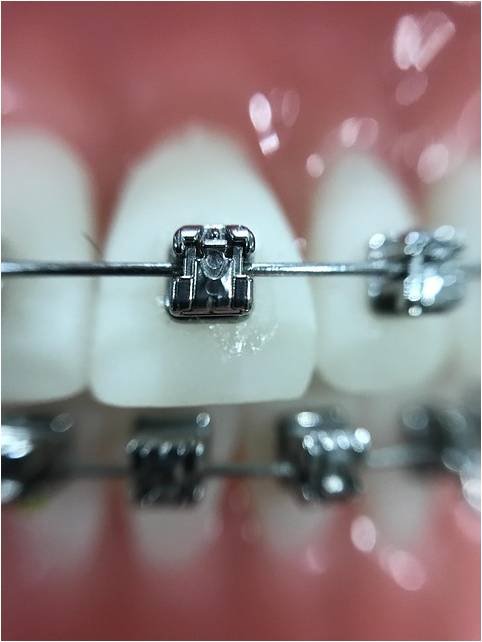

Ortodontia

Planejamento e acompanhamento durante todo o período de tratamento

Por que usar um aparelho ortodôntico se já sou adulto?

Existem diversas razões importantes para usar aparelho ortodôntico na fase adulta, que vão muito além da estética. Os tratamentos hoje são mais discretos e eficientes, e não há limite de idade para realinhar os dentes

Qual o tempo médio de um tratamento ortodôntico?

O tempo médio de um tratamento ortodôntico varia de 12 a 36 meses, com a maioria dos casos ficando entre 18 e 24 meses. A duração exata depende da complexidade do caso, como a gravidade da má oclusão, necessidade de extração de dentes, resposta individual do organismo e colaboração do paciente.